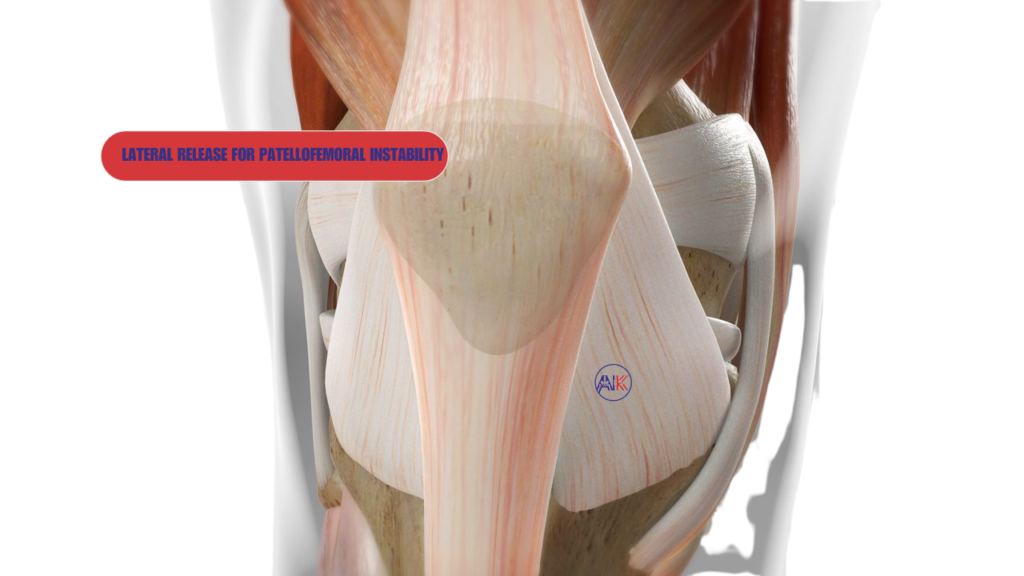

Lateral Release

A lateral release involvesDr Keeley cutting the tight lateral retinaculum on the outer side of your kneecap, which can help to realign the patella and reduce lateral pull, alleviating pain and preventing further dislocations.